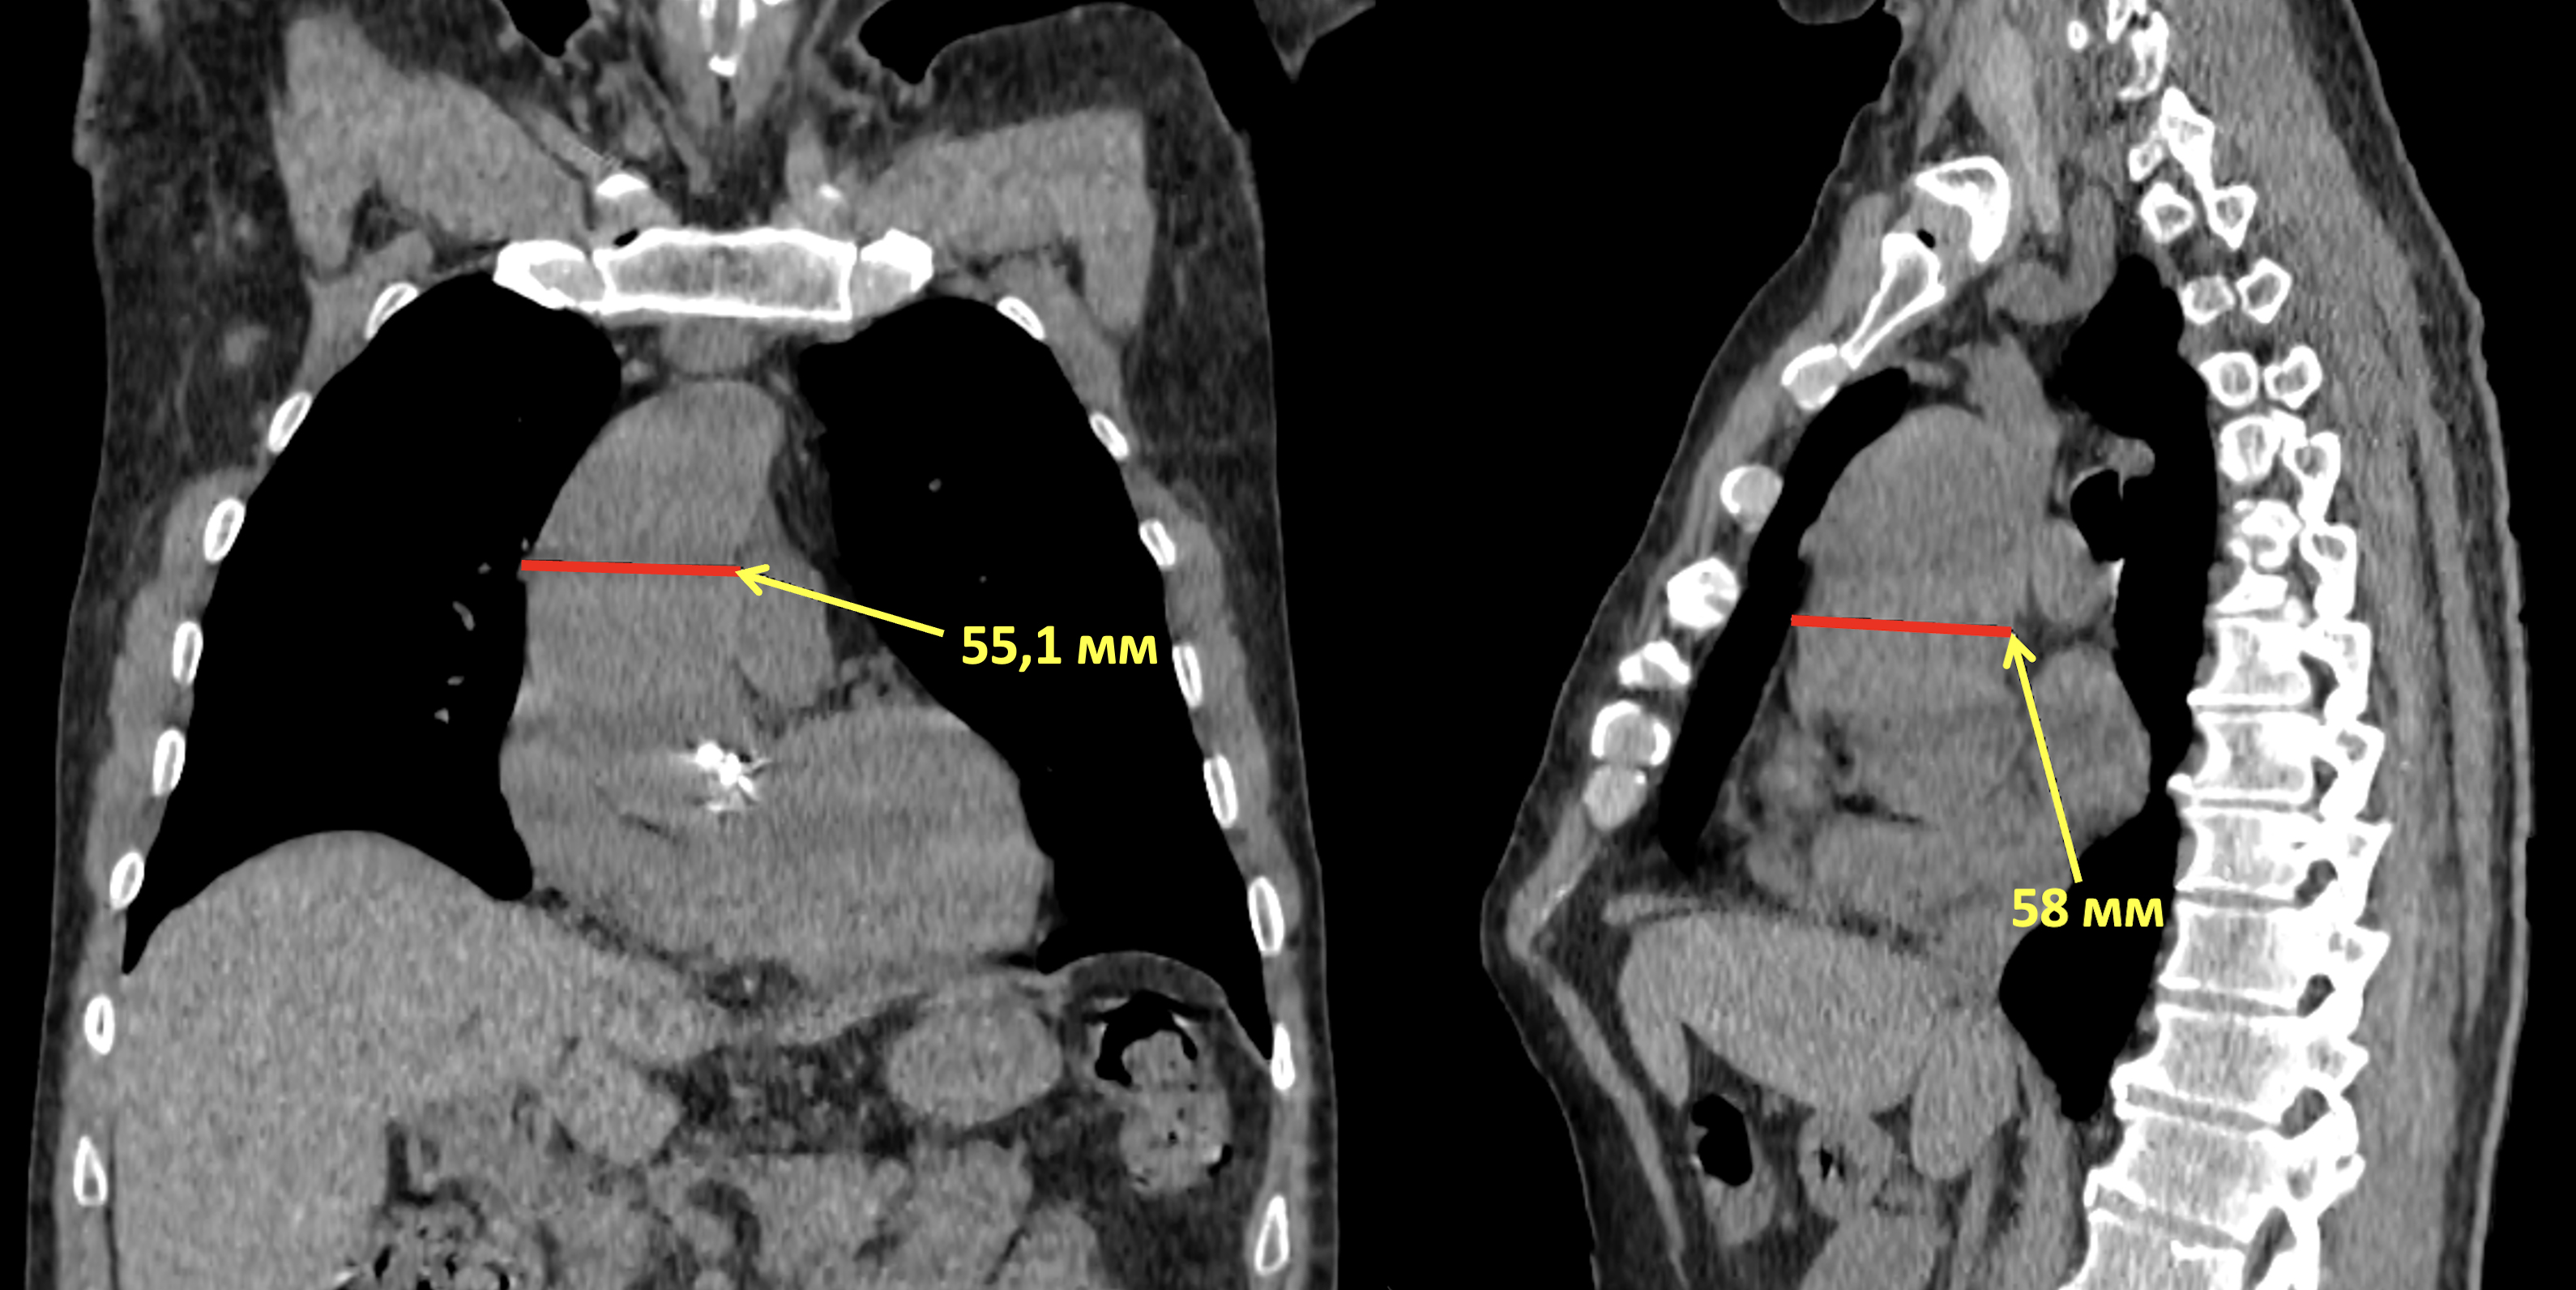

Рис. 1. Компьютерная томография органов грудной полости. Аневризма восходящей аорты: а — прямая проекция, максимальный диаметр аорты — 55,1 мм; б — боковая проекция, максимальный диаметр аорты — 58 мм

Fig. 1. Computed tomography of the chest cavity organs. Aneurysm of the ascending aorta: а — frontal view, maximum diameter of aorta is 55.1 mm; б — lateral view, maximum diameter of aorta is 58 mm

Многосрезовая мультиспиральная компьютерная томография (МСКТ) органов грудной полости (10.04.2024). КТ-признаки умеренных проявлений бронхиальной обструкции. Определяется аневризма восходящего отдела аорты до 58 мм (рис. 1). Сердце увеличено в размерах за счет всех камер. Отмечается кальцинация аортального клапана. Жидкости в полости перикарда и в плевральных полостях нет. Выявляются двусторонние плевроапикальные наслоения и непротяженные плевродиафрагмальные спайки. Проявления дегенеративно-дистрофических изменений грудного отдела позвоночника, системного остеопороза. В мягких тканях подключичной области справа определяются кальцинаты. КТ-данных за наличие объемного процесса, вторичных изменений в органах грудной полости не получено.

Наиболее тяжелым осложнением сифилитического мезаортита является аневризма аорты, в диагностике которой основное значение имеют визуализационные методы исследования — эхокардиография, МРТ сердца, МСКТ аорты. В норме верхняя граница нормального значения диаметра корня аорты составляет 40 мм у мужчин и 34 мм у женщин [6]. Кроме расширения аорты, чаще всего в восходящей части, при сифилисе обнаруживают уплотнение и кальциноз в области ее основания и стенок. В представленном нами случае клинически бессимптомная аневризма явилась случайной находкой при обследовании пациента в связи с возникшей патологией почек. Считается, что в группу высокого риска развития аневризмы аорты входят лица с двустворчатым аортальным клапаном, к числу которых относится и наблюдавшийся нами пациент. По данным МСКТ диаметр восходящего отдела аорты у него достигал 58 мм (см. рис. 1). Аневризмы восходящей аорты обычно считаются большими, если их диаметр превышает 55 мм или индекс диаметра аорты (отношение диаметра к площади поверхности тела) ≥ 2,75 см/м2 (в описываемом случае — 2,87 см/м2). При увеличении диаметра восходящей аорты более 60 мм возрастает риск разрыва ее стенки, чему способствуют артериальная гипертензия, гипергликемия и гиперхолестеринемия — неблагоприятные факторы, сформировавшиеся у пациента на фоне нефротического синдрома.